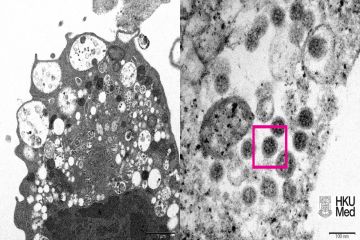

Phát hiện biến thể mới "siêu lây nhiễm" của HIV, dễ thành AIDS hơn

Thứ Ba, 15/02/2022Tin vui là các phương pháp điều trị sẵn có vẫn mang lại khả năng điều trị tương đương đối với biến thể mới.